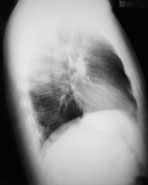

Ein 41-jähriger Mann sucht Sie auf, weil er zum dritten Mal in diesem Winter erkältet ist und dieses Mal sogar mit Fieber. Er gibt ausserdem an, etwas trockenen Husten zu haben. Ausserdem besteht seit Wochen eine Sinusitis, die nicht so recht abheilen will.

Gewichtsverlust wird verneint. Der Patient ist Nichtraucher und fühlte sich bis anhin gesund.

Die Lungenperkussion und -auskultation ist unauffällig. Das Labor zeigt eine Leukozytose ohne Linksverschiebung und ein CRP von 97 mg/dl. Hier das Röntgenbild der Lunge:

Thorax seitlich

Welche Befunde fallen Ihnen auf?

Es ist klar, dass aufgrund dieses Befundes keine Diagnose gestellt werden kann. Welche Diagnose ist aufgrund der Klink und des radiologischen Befundes am wahrscheinlichsten?